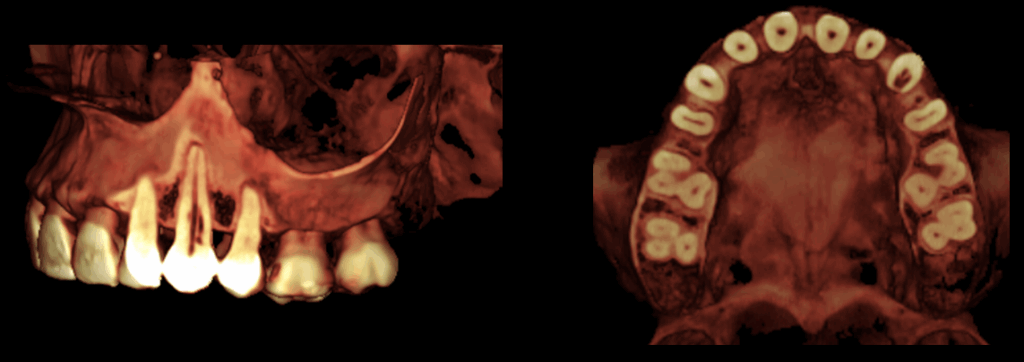

CORTES TRANSAXIALES

CORTES TANGENCIALES

En la tomografía computarizada de haz cónico se identifica en la pieza 23 una imagen isodensa que compromete las paredes radiculares mesial, distal y palatina a nivel del tercio cervical, en estrecha proximidad con el conducto radicular. Asimismo, se observa un ensanchamiento del espacio del ligamento periodontal adyacente.

- Reabsorción cervical externa en pieza 23.